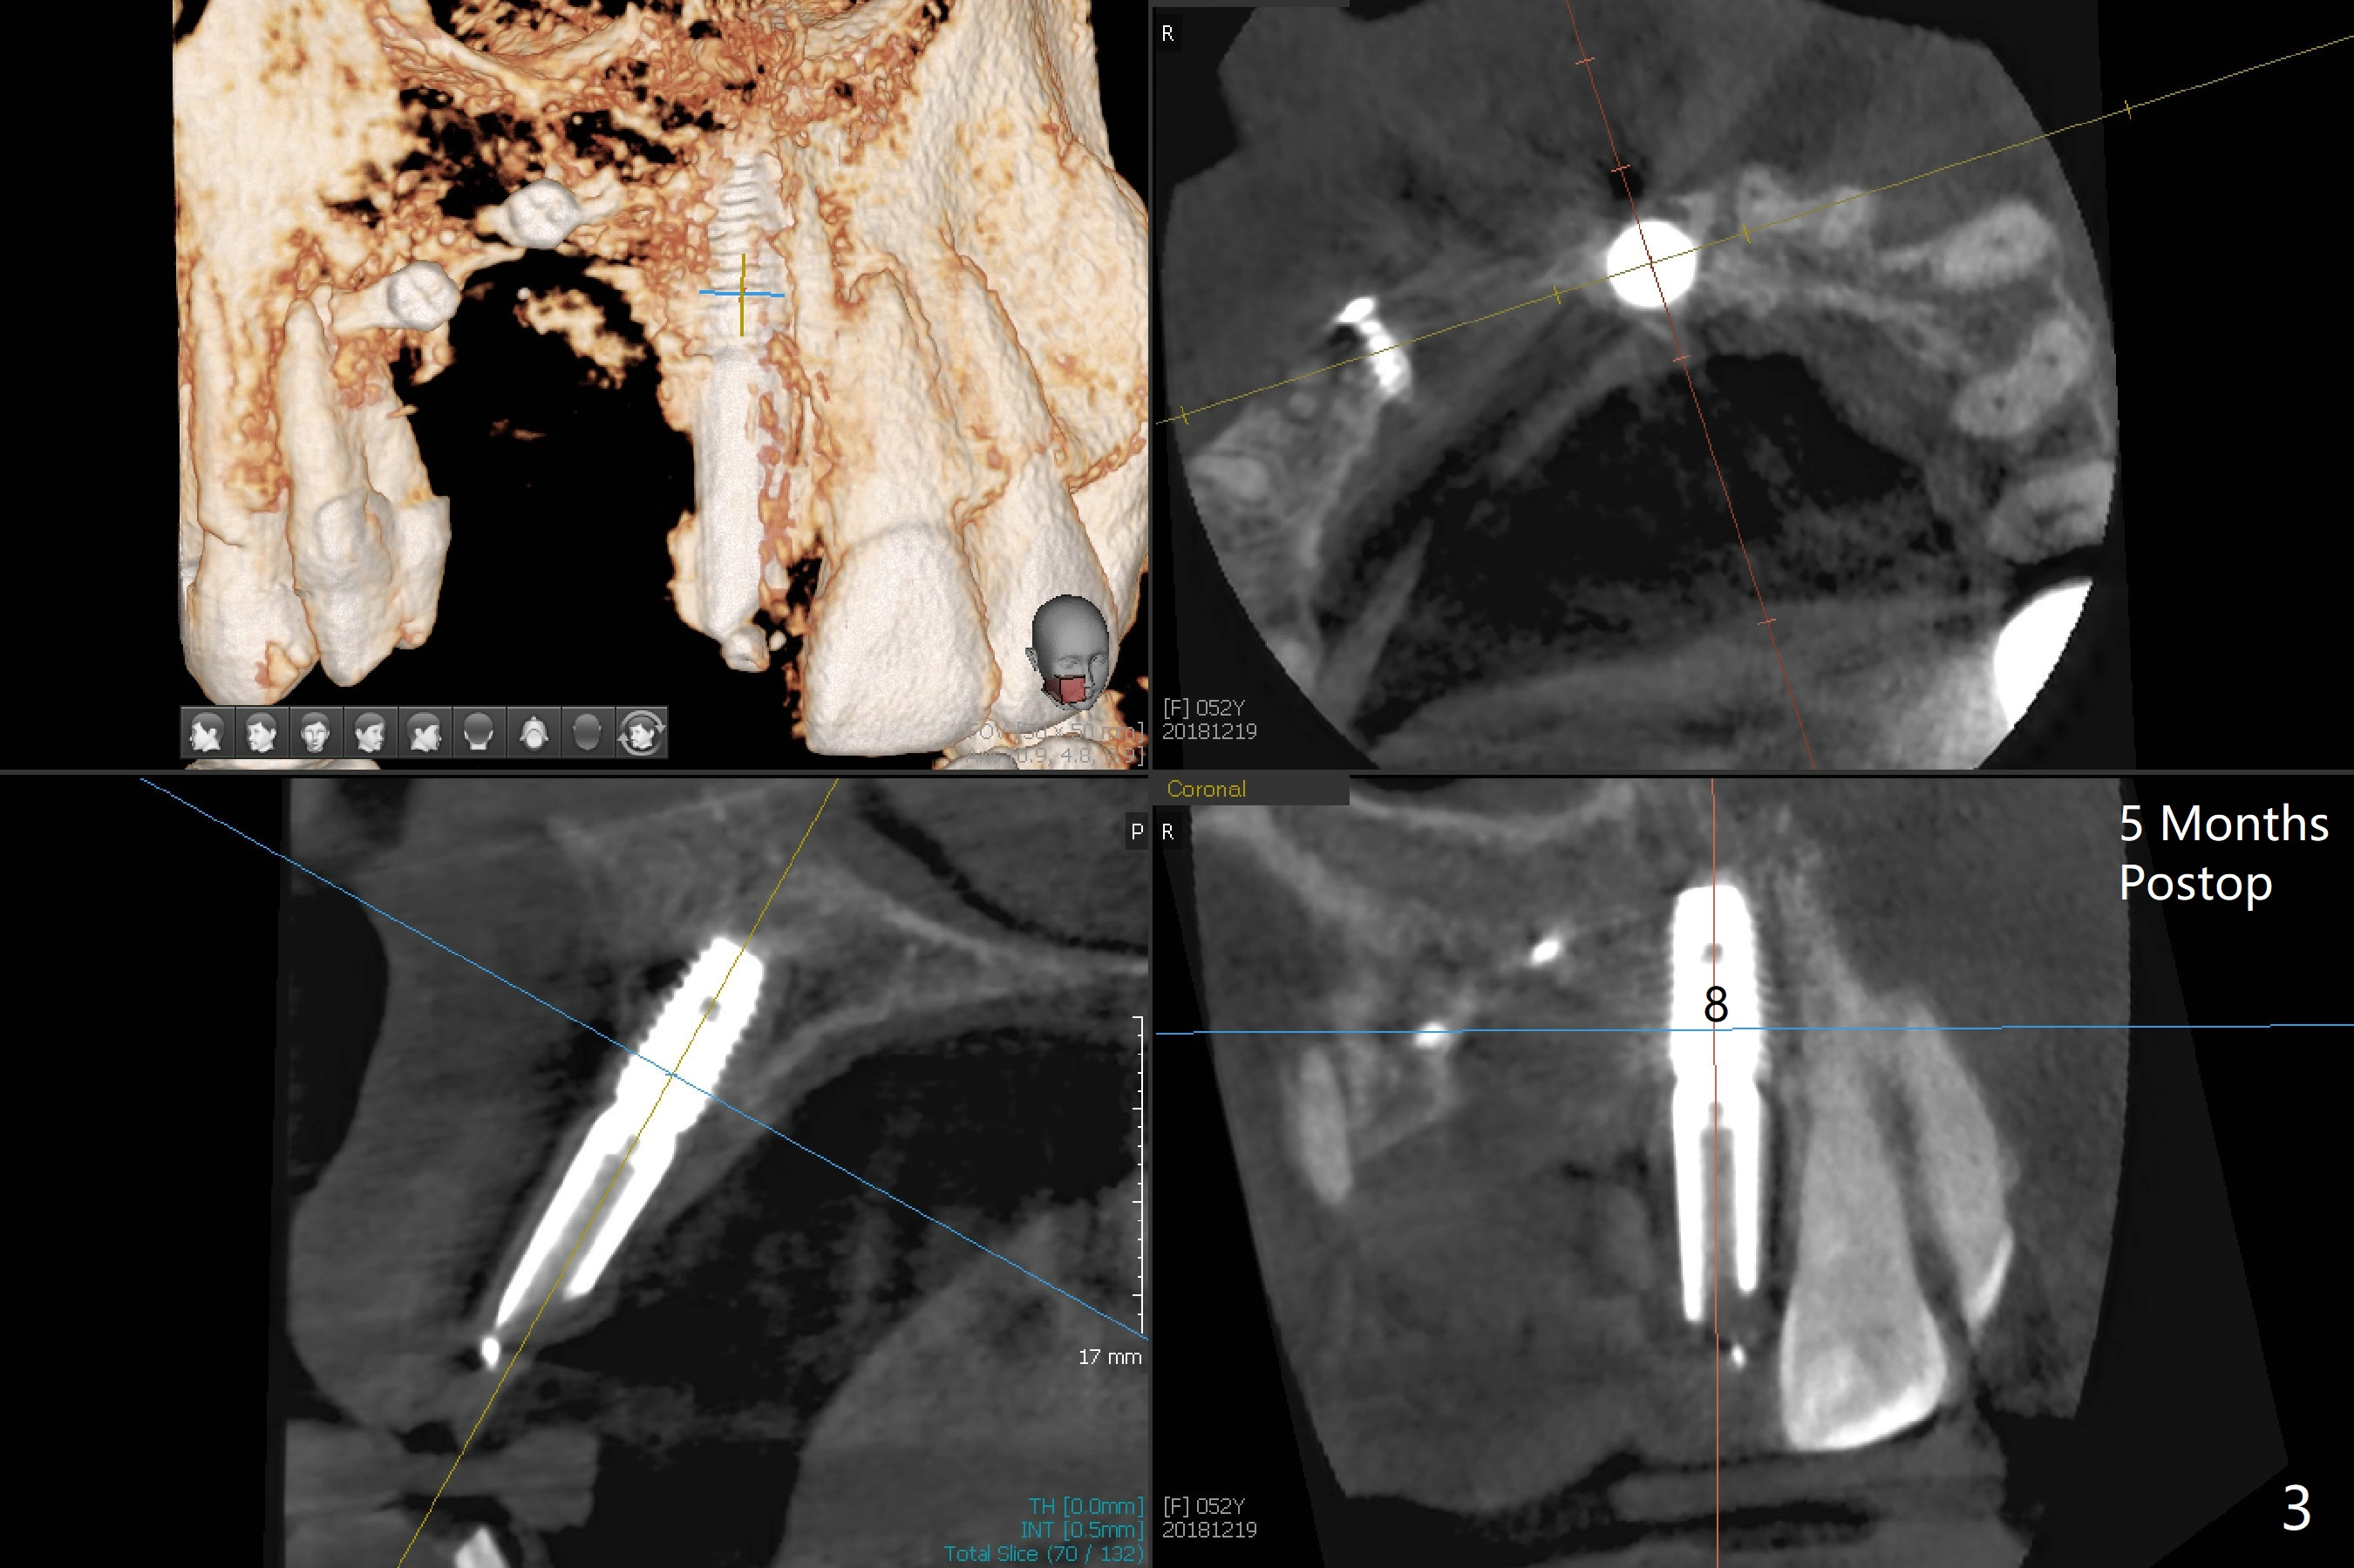

Narrow Implants at #6 and 7

Four months post bone graft with tenting screws at #6 and 7 and implant re-placement at #8, the ridge at #6 and 7 appears to widen slightly, appropriate for narrow implants (Fig.1,2). Guide will be fabricated. The implant at #8 seems to have osteointegrated (Fig.3) with distal gingival recession (Fig.4). One year 5 months later, the tooth #5 is infected with apparently mesial bone loss (Fig.5 *) and papillary erythema and edema (Fig.6). However the pockets are not deep. A gingival embrasure is created between #5 and 6 for self cleansing. The latter does not work. Implants will be placed at #5 and 7 (Fig.7,8).